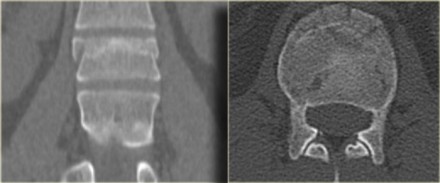

On the left a coronal reconstruction and an axial image at the level of the fracture.

Continue with the MR.

The MR images show bone marrow edema in the involved vertebral body, but no additional soft tissue injury.

Based on the fact that the MR did not show any additional findings, this patient was treated as having a single column injury.

Consultation with orthopedic surgery recommended conservative management with a TLSO brace.

Nowadays there is a tendency to treat these thoracolumbar injuries

conservatively, even if there is slight involvement of the middle

column.

The role of MRI in these cases is not clear yet.